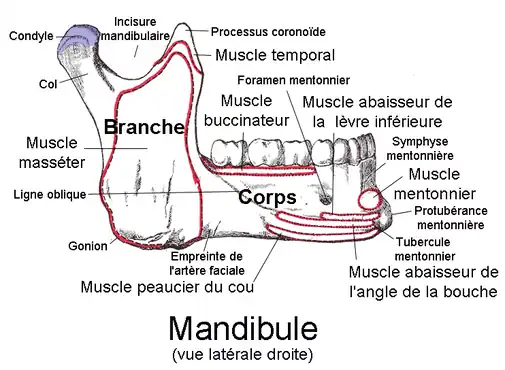

Classiquement, on distingue les fractures de mandibule en plusieurs catégories qui se regroupent plus ou moins:

Localisation

Portion dentée

- Symphysaire,

- parasymphysaire,

- branche horizontale ou corpus,

- angle.

Ramus ou branche montante

- Ramus vrai,

- coroné.

Condyle